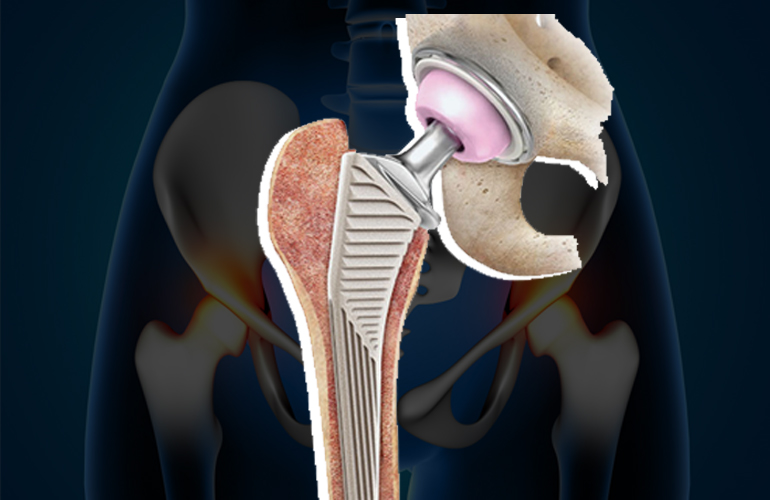

Revision hip replacement involves removing the old or damaged implant and replacing it with a new, advanced prosthesis to restore stability and comfortable movement. This surgery is more complex than primary hip replacement and requires specialized skills, precision, and careful planning.

Revision hip replacement requires a high level of expertise, and Dr. Akash Saraogi is known for successfully treating complex hip cases with advanced surgical techniques. At HappyKnees, we use specialized revision implants, bone reconstruction techniques, 3D imaging, and minimally invasive approaches wherever possible to ensure optimal patient outcomes.